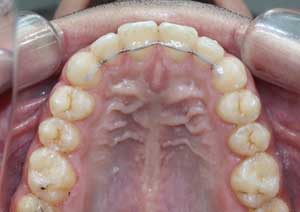

Traitement : Dans ce cas, nous avons eu recours à la mise en place de cales postérieures en résine bleue au niveau des premières molaires maxillaires, Elles ont permis de séparer temporairement les mâchoires afin de laisser les dents du haut se replacer correctement devant celles du bas, corrigeant ainsi le cross-bite antérieur.

Par la suite, ces cales ont été déplacées sur les faces palatines des incisives maxillaires dans le but d’optimiser l’articulé postérieur, notamment au niveau des molaires droites, qui présentaient également un articulé inversé.